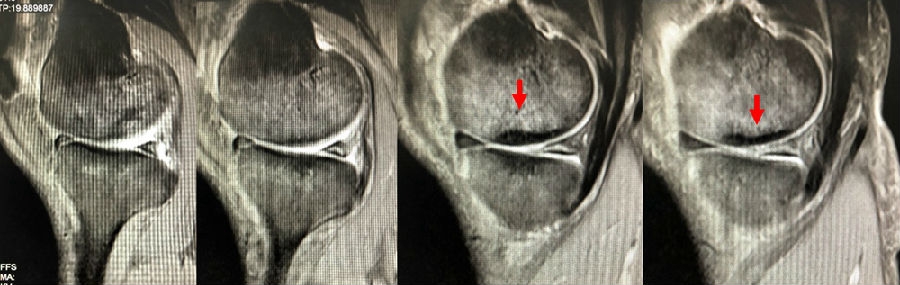

病例1:男,64岁,主诉左膝关节内侧疼痛6年余。MR提示骨坏死区占比为33.28%,矢状位病变区域前后径为26.42mm,半月板相对突出百分比(RPE)31.78%,同时存在胫骨侧来源的下肢内翻畸形(MPTA83°),关节线会聚角2°。

行关节镜检查+软骨摘除+微骨折+HTO术,术后随访2年恢复良好,活动自如,行走时无左膝关节疼痛不适。